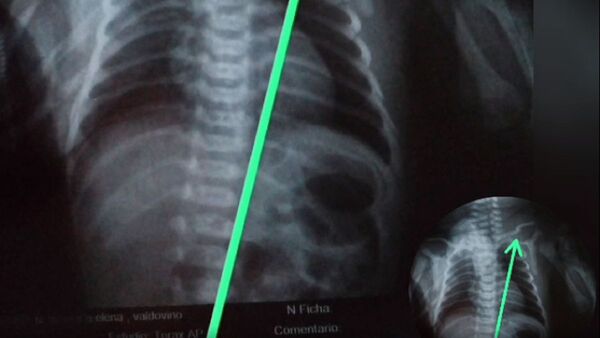

Papá denunció que fracturaron clavícula a su beba al nacer

El padre de familia comentó que la beba nació el sábado, pero recién ayer le informaron sobre lo ocurrido. ...[Leer más]